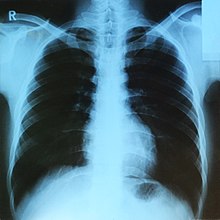

X-ray

Do you think you need an X-ray? Read on to learn more about this common procedure.

X-ray imaging has been used for many years to give physicians a glimpse inside your body at your bones, muscles and more without having to make an incision. This imaging test provides doctors with the ability to diagnose, treat and monitor a variety of medical conditions. X-ray machines use electromagnetic radiation, so there is some risk as high doses of these invisible rays can cause radiation burns or even cancer. However, the diagnostic benefits of X-ray imaging far outweigh these concerns.

Using specialized equipment, images are created by sending X-ray particles called photons through the body. X-ray film or computers are then used to capture the images of your body’s internal structures that are produced. Dense structures, like bone or metal, appear white in the images because they block most of the X-ray particles from traveling through them. Muscles, fat and fluids, however, appear in various shades of gray. Structures that contain air look black.